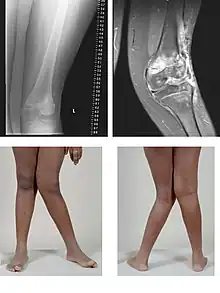

| Valgus deformity of the knee (genu valgum), seen in MRI and photograph | |

- Knee: genu valgum (from Latin genu = knee) – the tibia is turned outward in relation to the femur, resulting in a knock-kneed appearance. Common causes of valgus knee (colloquially "knock-knee") in adults include arthritis of the knee and traumatic injuries.